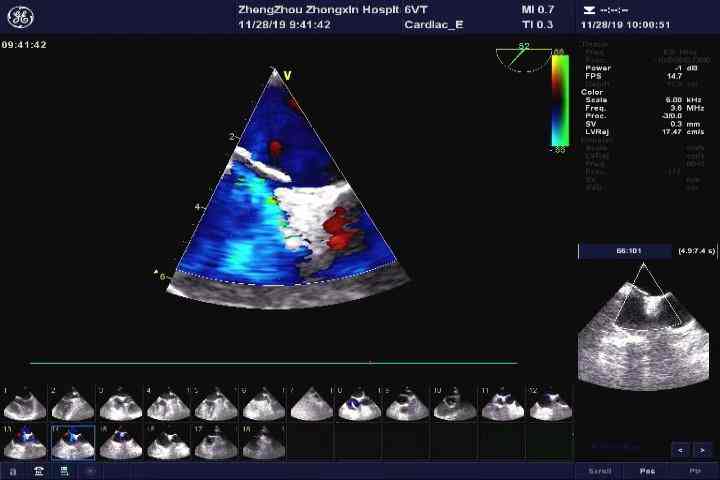

医院立即为娜娜启动脑卒中救治绿色通道,紧急为其做了磁共振成像(MRI)。结果显示“右侧丘脑急性脑梗死,颅内大动脉闭塞”。由于娜娜错过了脑卒中溶栓的最佳时间,介入二线为娜娜选择了目前最适合的动脉内取栓。手术很成功,还没下手术床的娜娜左手指已经可以活动了。娜娜是个青春活力的青年人,为什么会突发脑卒中呢?神经内科大夫为其安排了发泡试验联合右心声学造影检查,考虑“卵圆孔未闭”,随后的经食管超声心动图检查结果也进一步印证了卵圆孔未闭的诊断。

经食管超声心动图检查结合右心声学造影是诊断卵圆孔未闭的“金标准”成像方式。右心声学造影被广泛用于诊断或排除心内或肺内右向左分流相关疾病。经食管超声可清晰地观察到卵圆孔未闭的位置、形状、边缘房间隔长度,测量卵圆孔未闭的静息直径和开放直径。